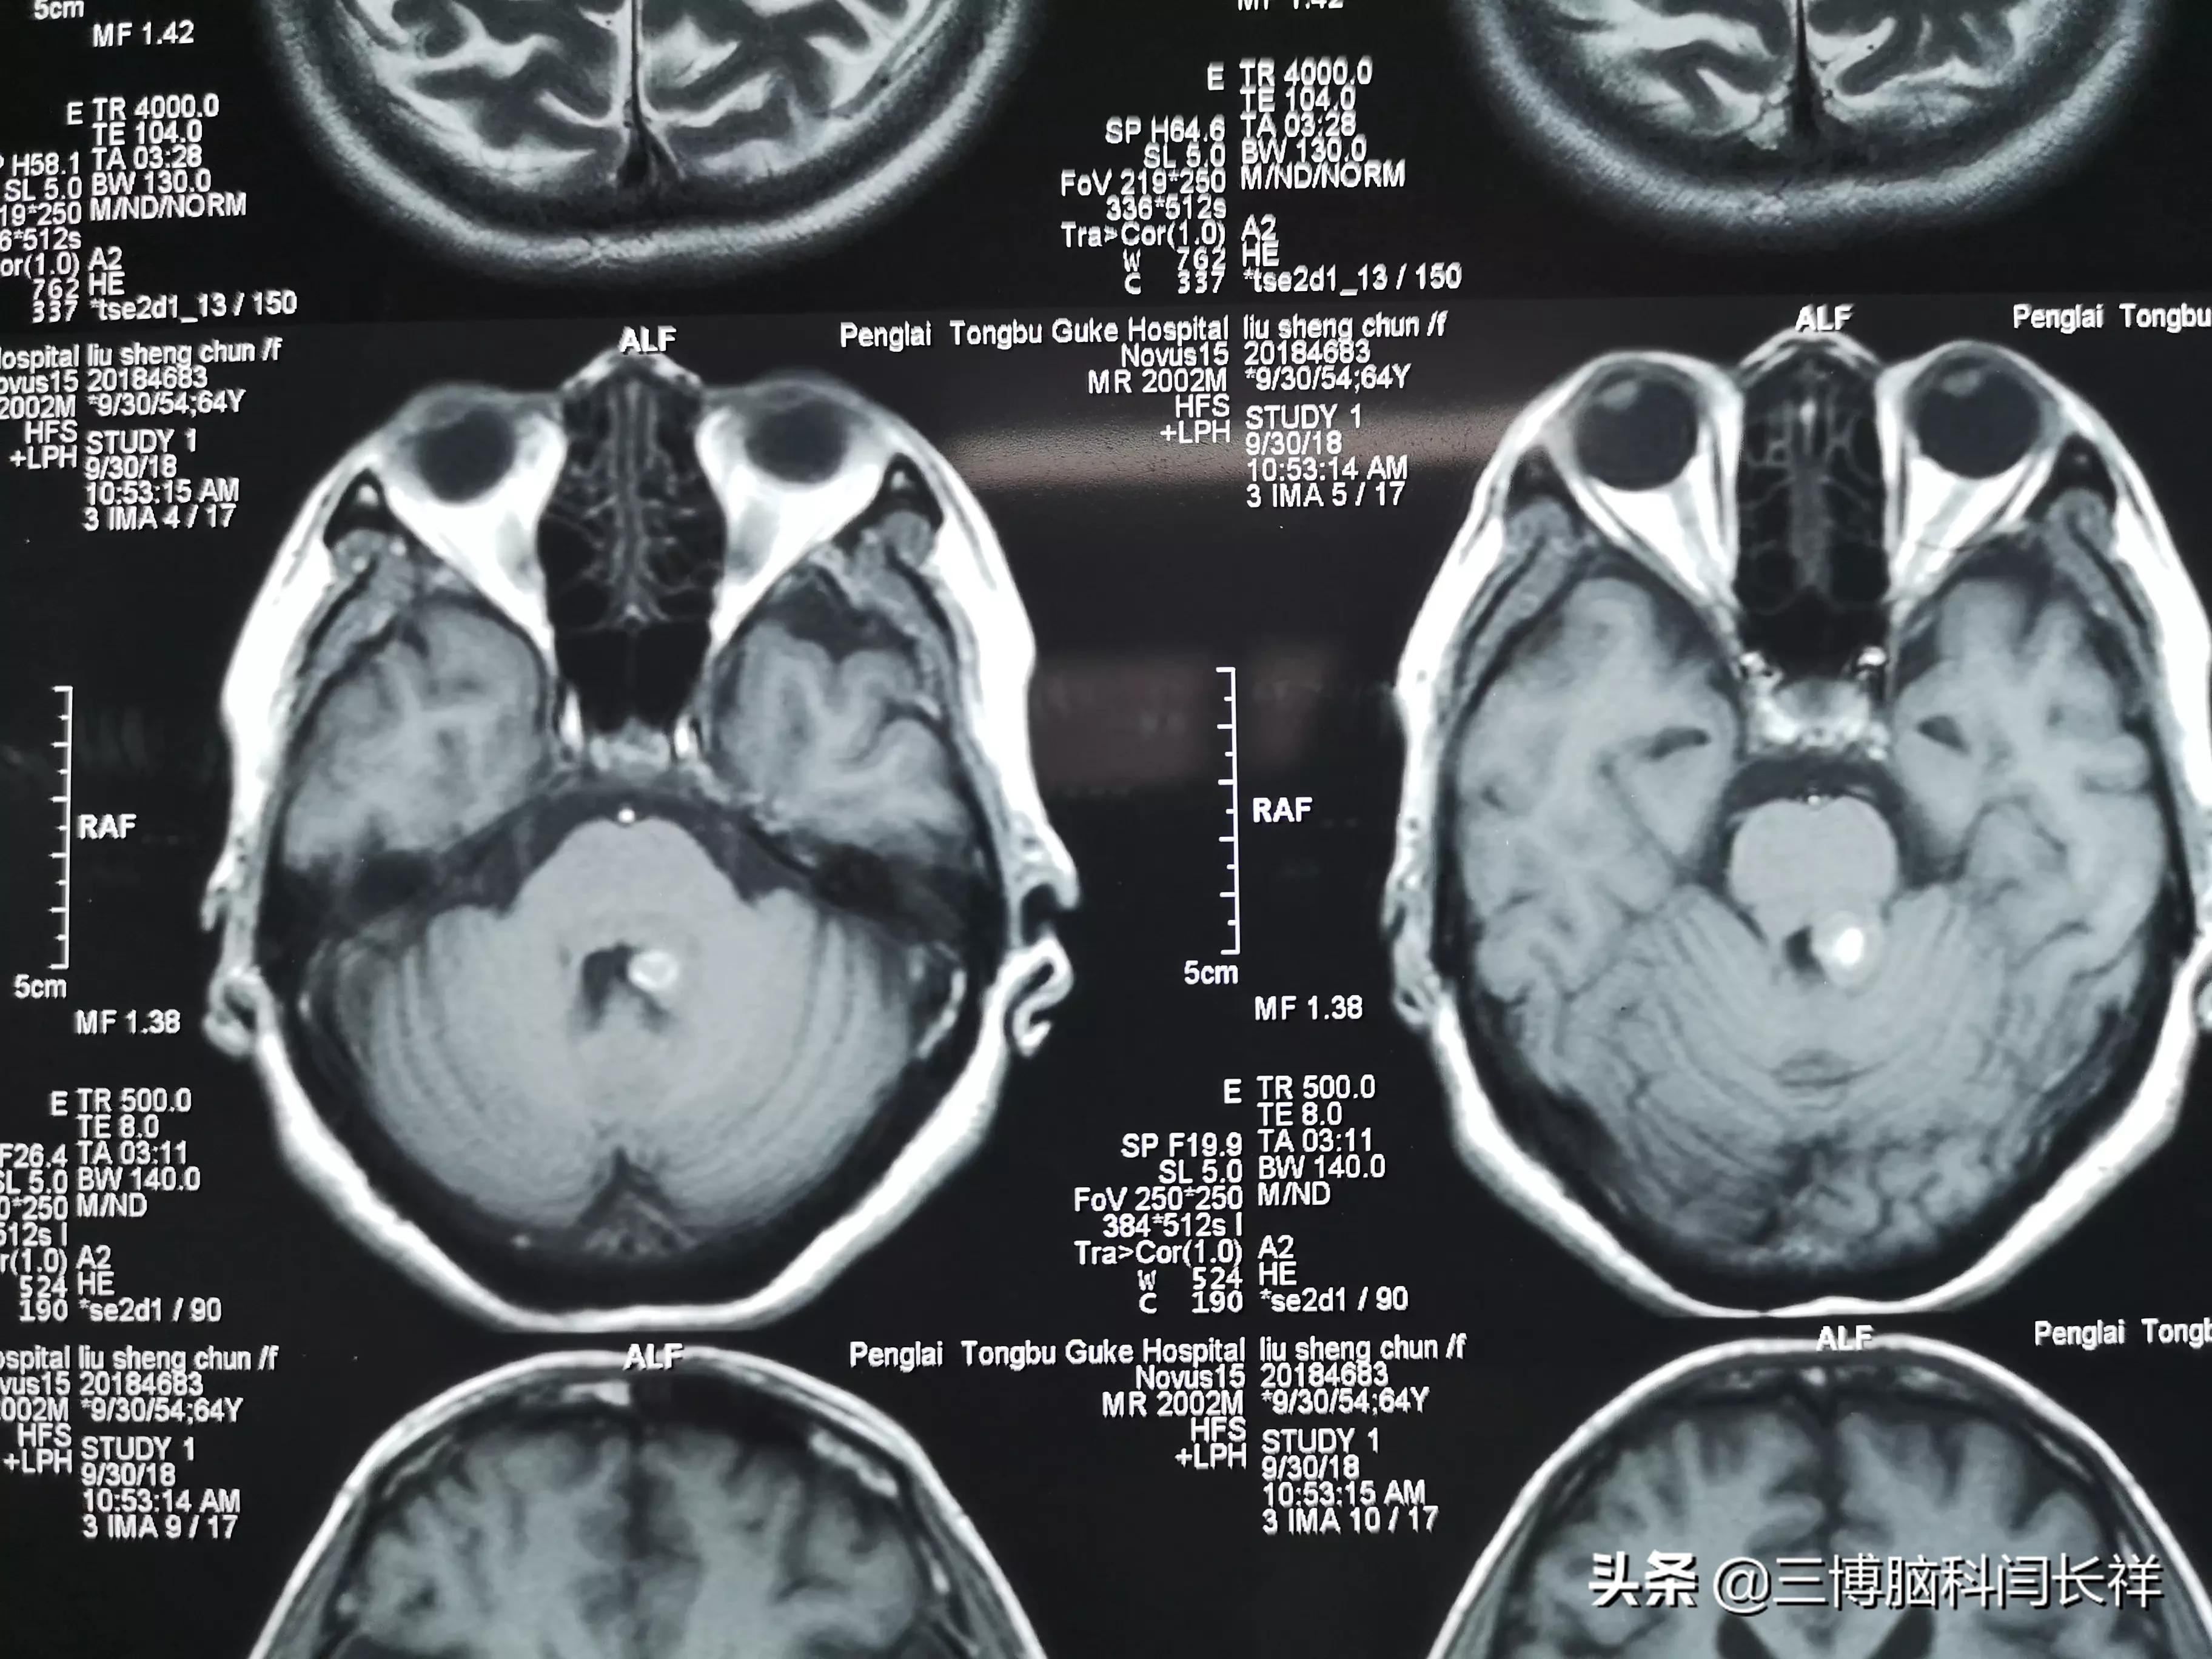

近期我做的典型手术病例4(脑干海绵状血管瘤) - 好大夫在线

关于脑干海绵状血管瘤